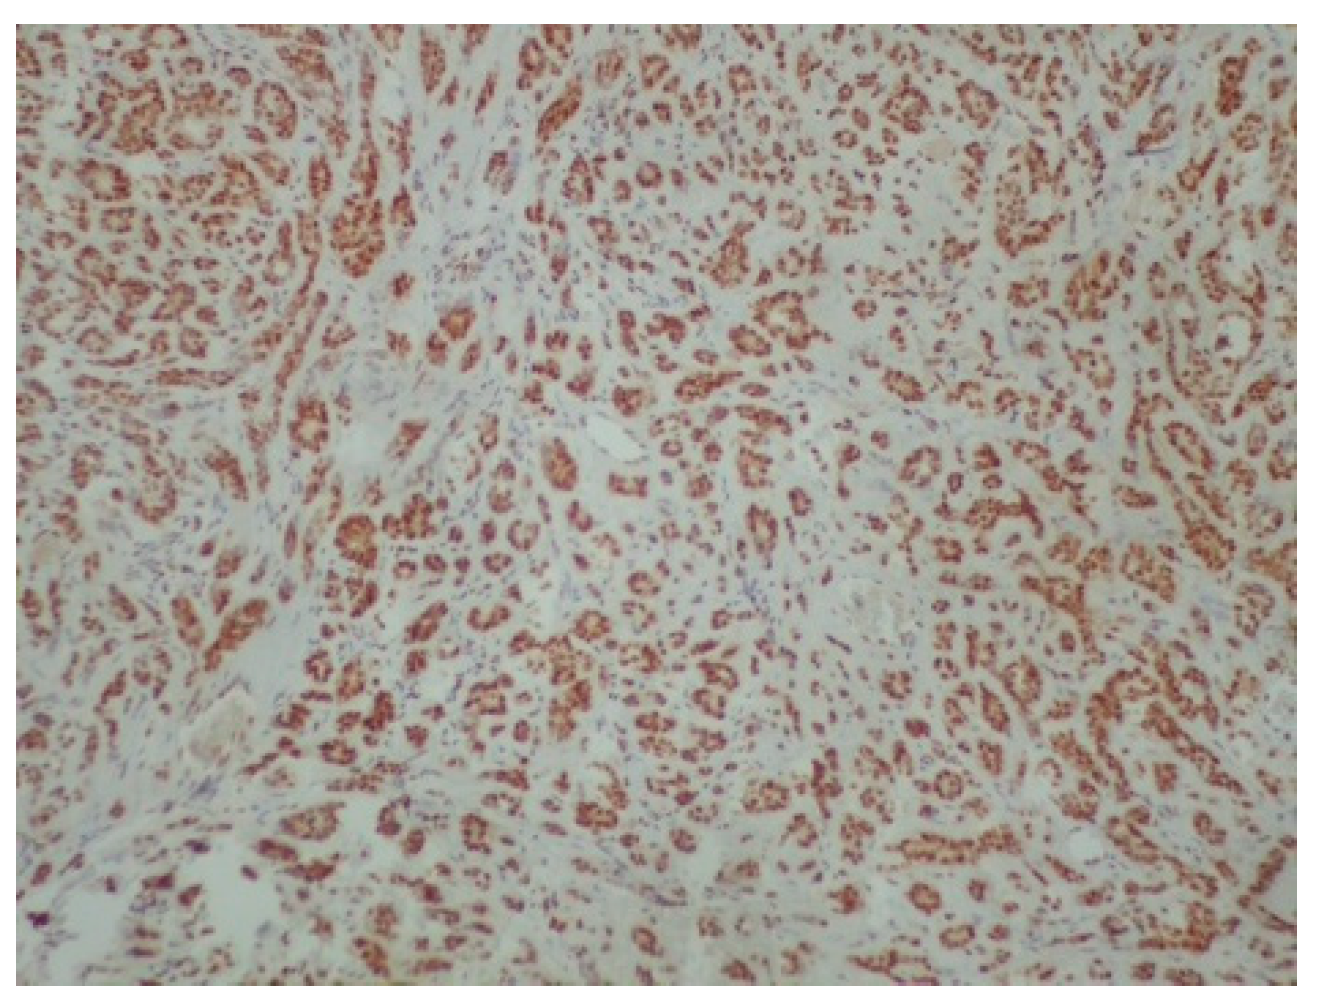

Figure 4.

Diffuse and intense positivity of neoplastic cells for cytokeratin 7 (immunoperoxidase ×100).